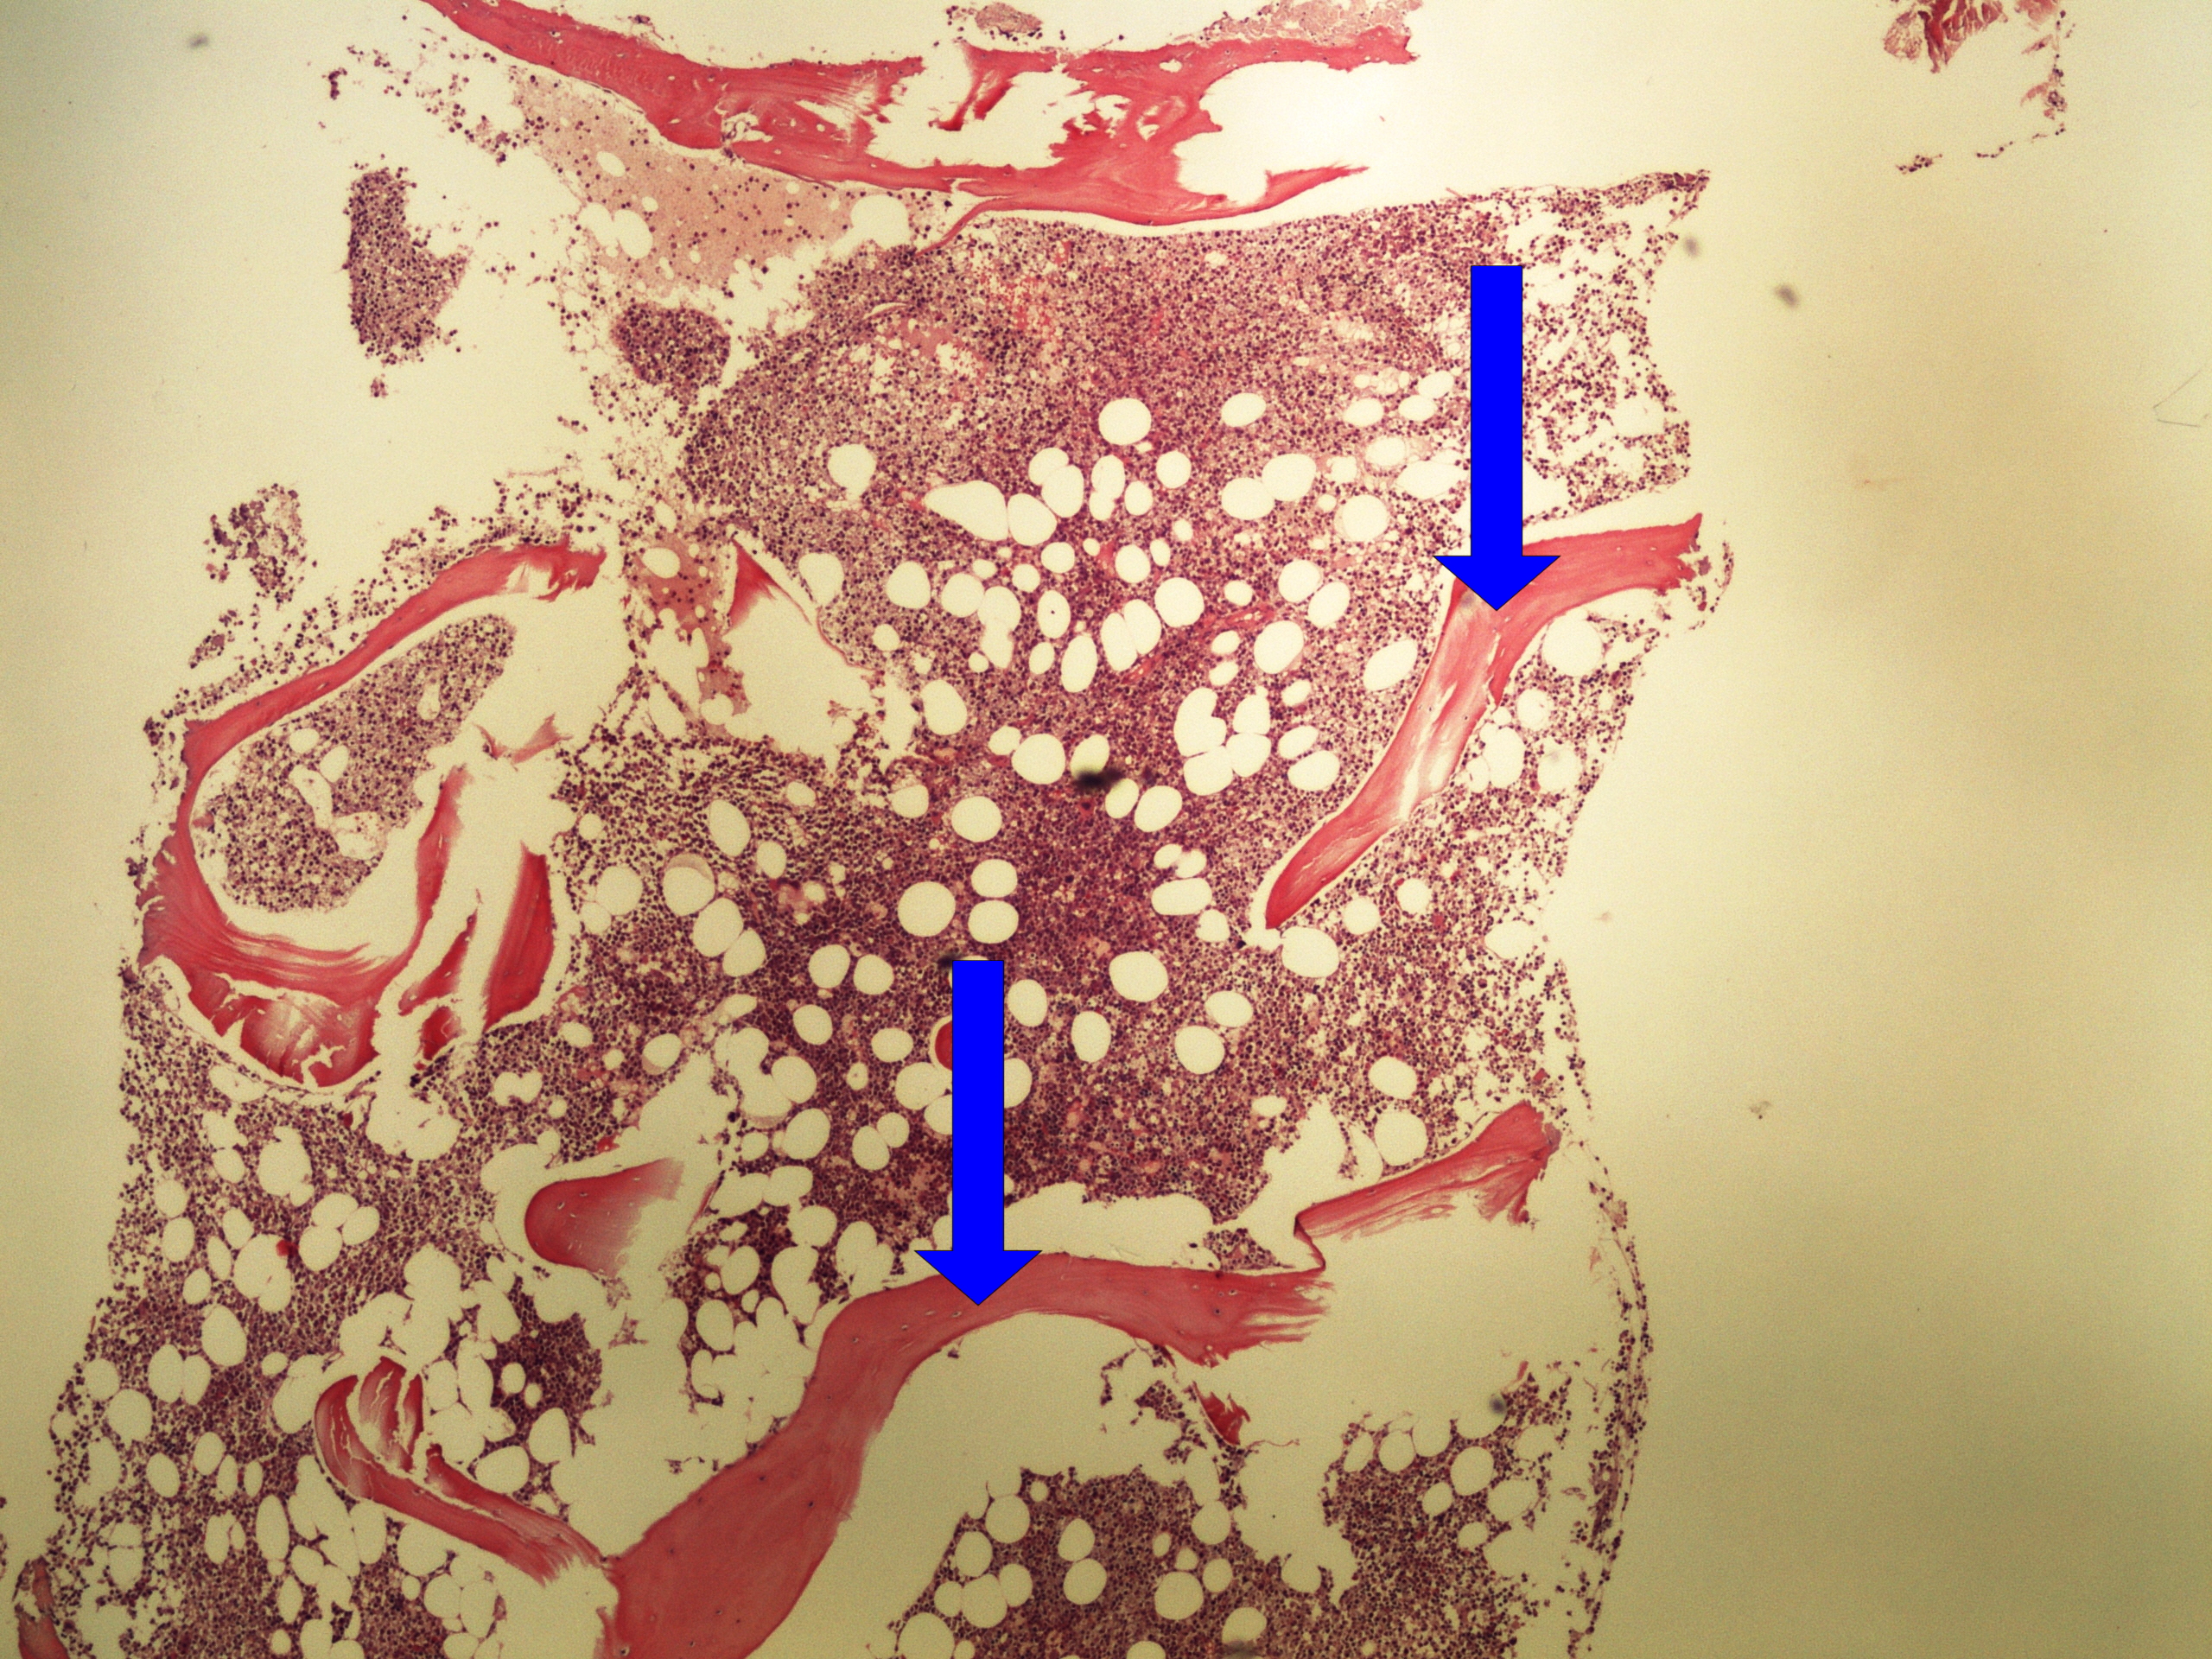

Preparát č.5 a č.6 - infiltrace kostní dřeně při CLL

Struktury

- peritrabekulární infiltrace malými lymfoidními elementy

- trabekuly